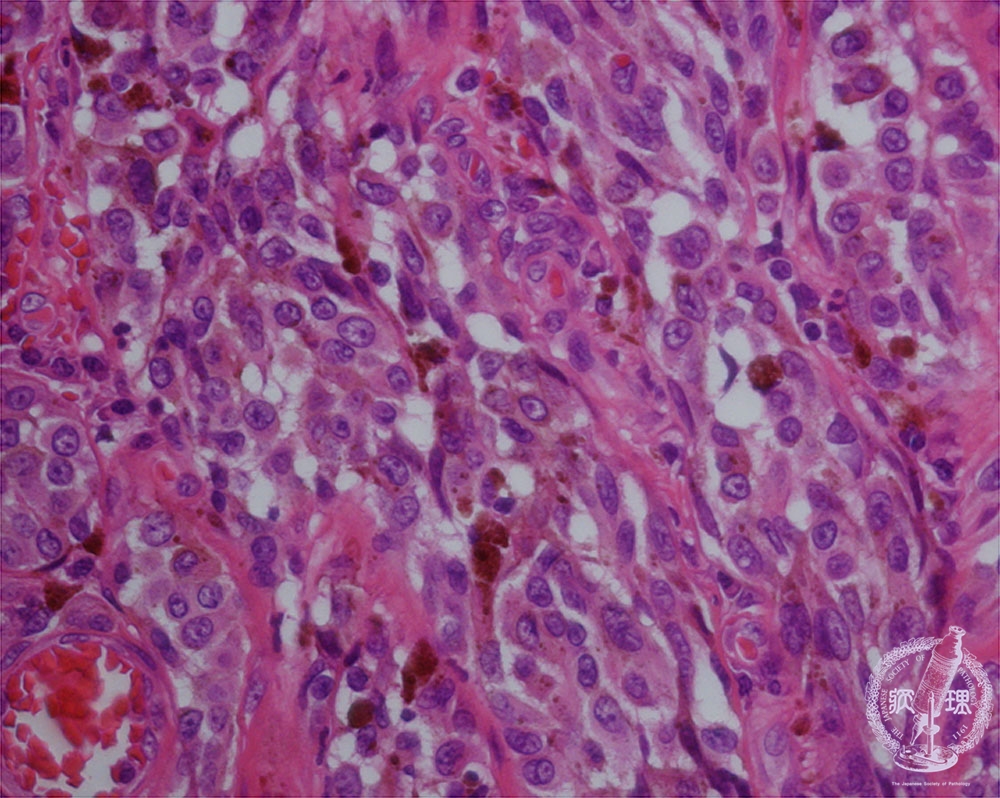

- ★(10)Malignant melanoma

Atypical melanocytes proliferate with anisokaryosis and large nucleoli. Melanin-production is usually but not necessarily seen (arrow).